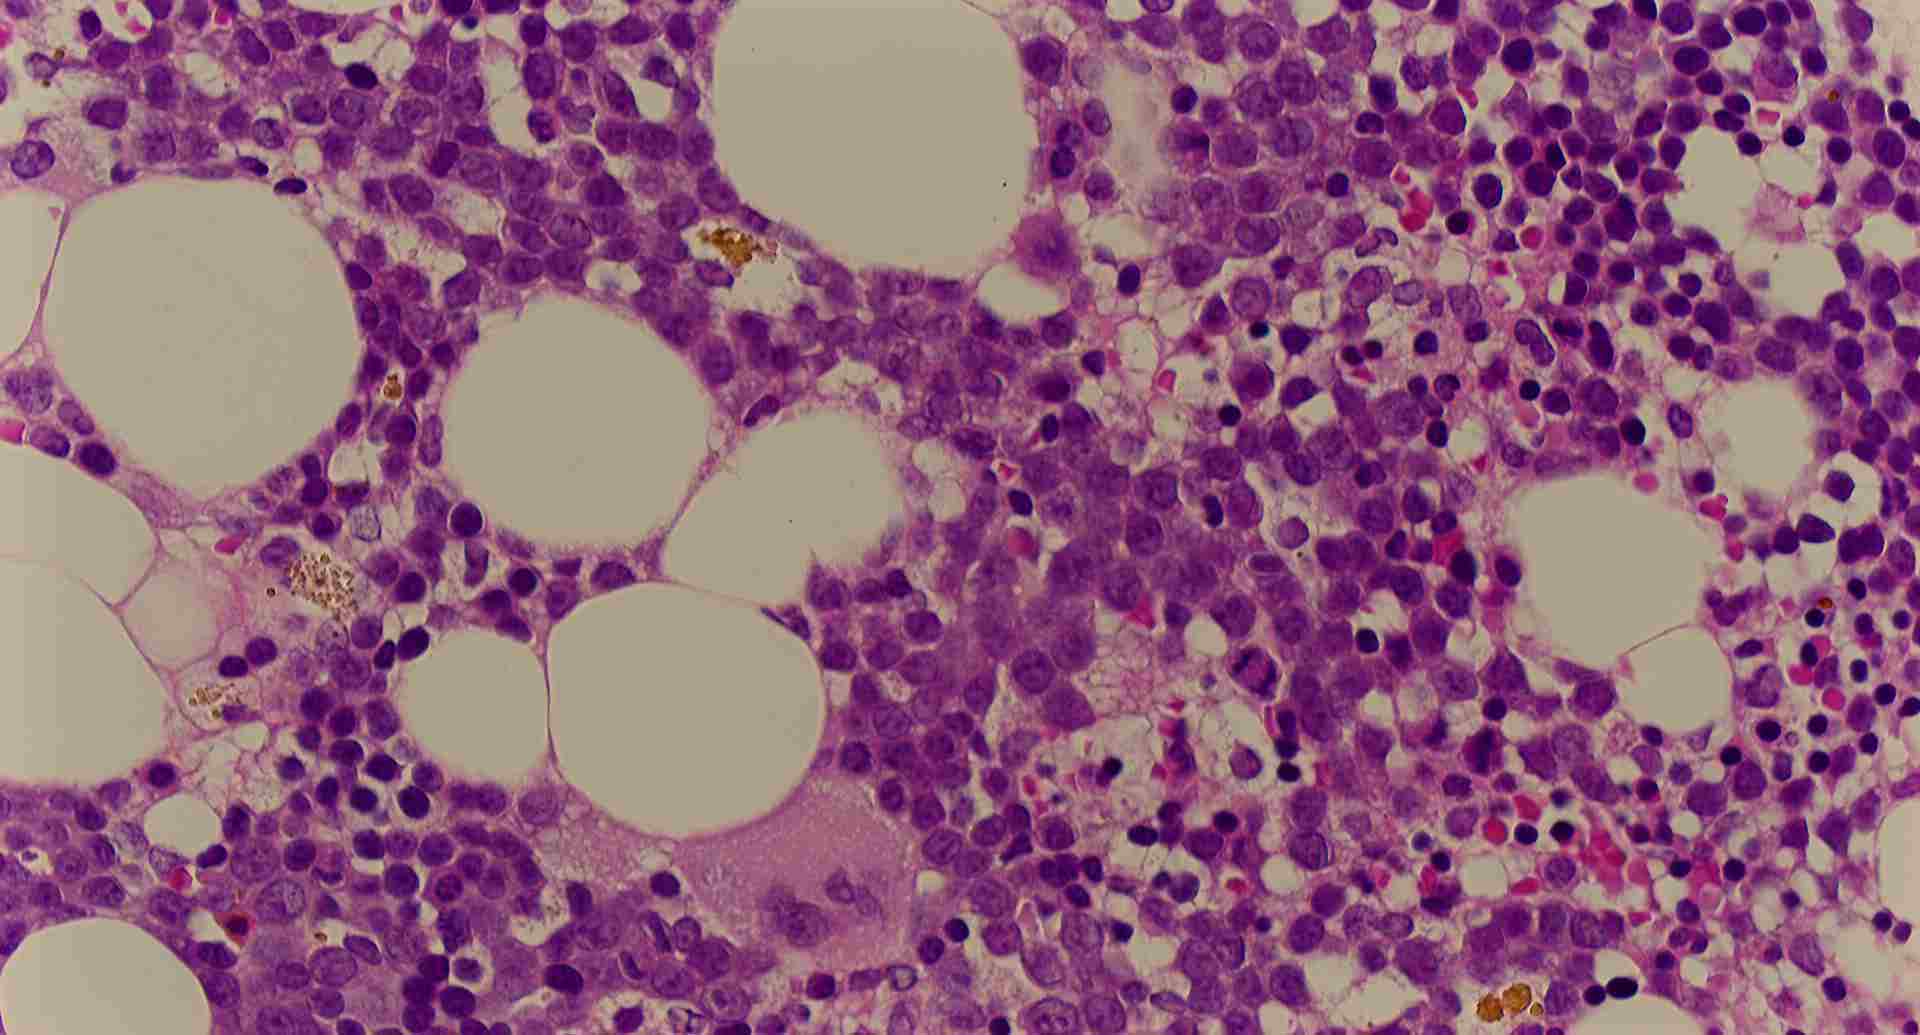

標本2